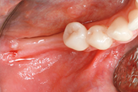

При планировании имплантологического лечения наиболее частой проблемой становится дефицит альвеолярной кости, которая служит базисом для удержания имплантата в теле челюстной кости.

Явления, которые происходят при отсутствии зуба в соответствующем сегменте кости, приводят к необходимости проведения костной пластики.

Челюстная кость после удаления зуба не испытывает функциональную нагрузку и с течением времени утрачивает свой объем, часто истончается.

И на момент восстановления утраченного зуба у пациента образовывается узкий атрофированный альвеолярный гребень.

Такая горизонтальная атрофия альвеолярной кости происходит как следствие экстракции зуба по причине некачественного эндодонтического лечения или из-за пародонтологических заболеваний.

Следует заметить, что убыль костной ткани по толщине гребня происходит значительно больше с вестибулярной (или щечной) стороны стенки альвеолярной ячейки.